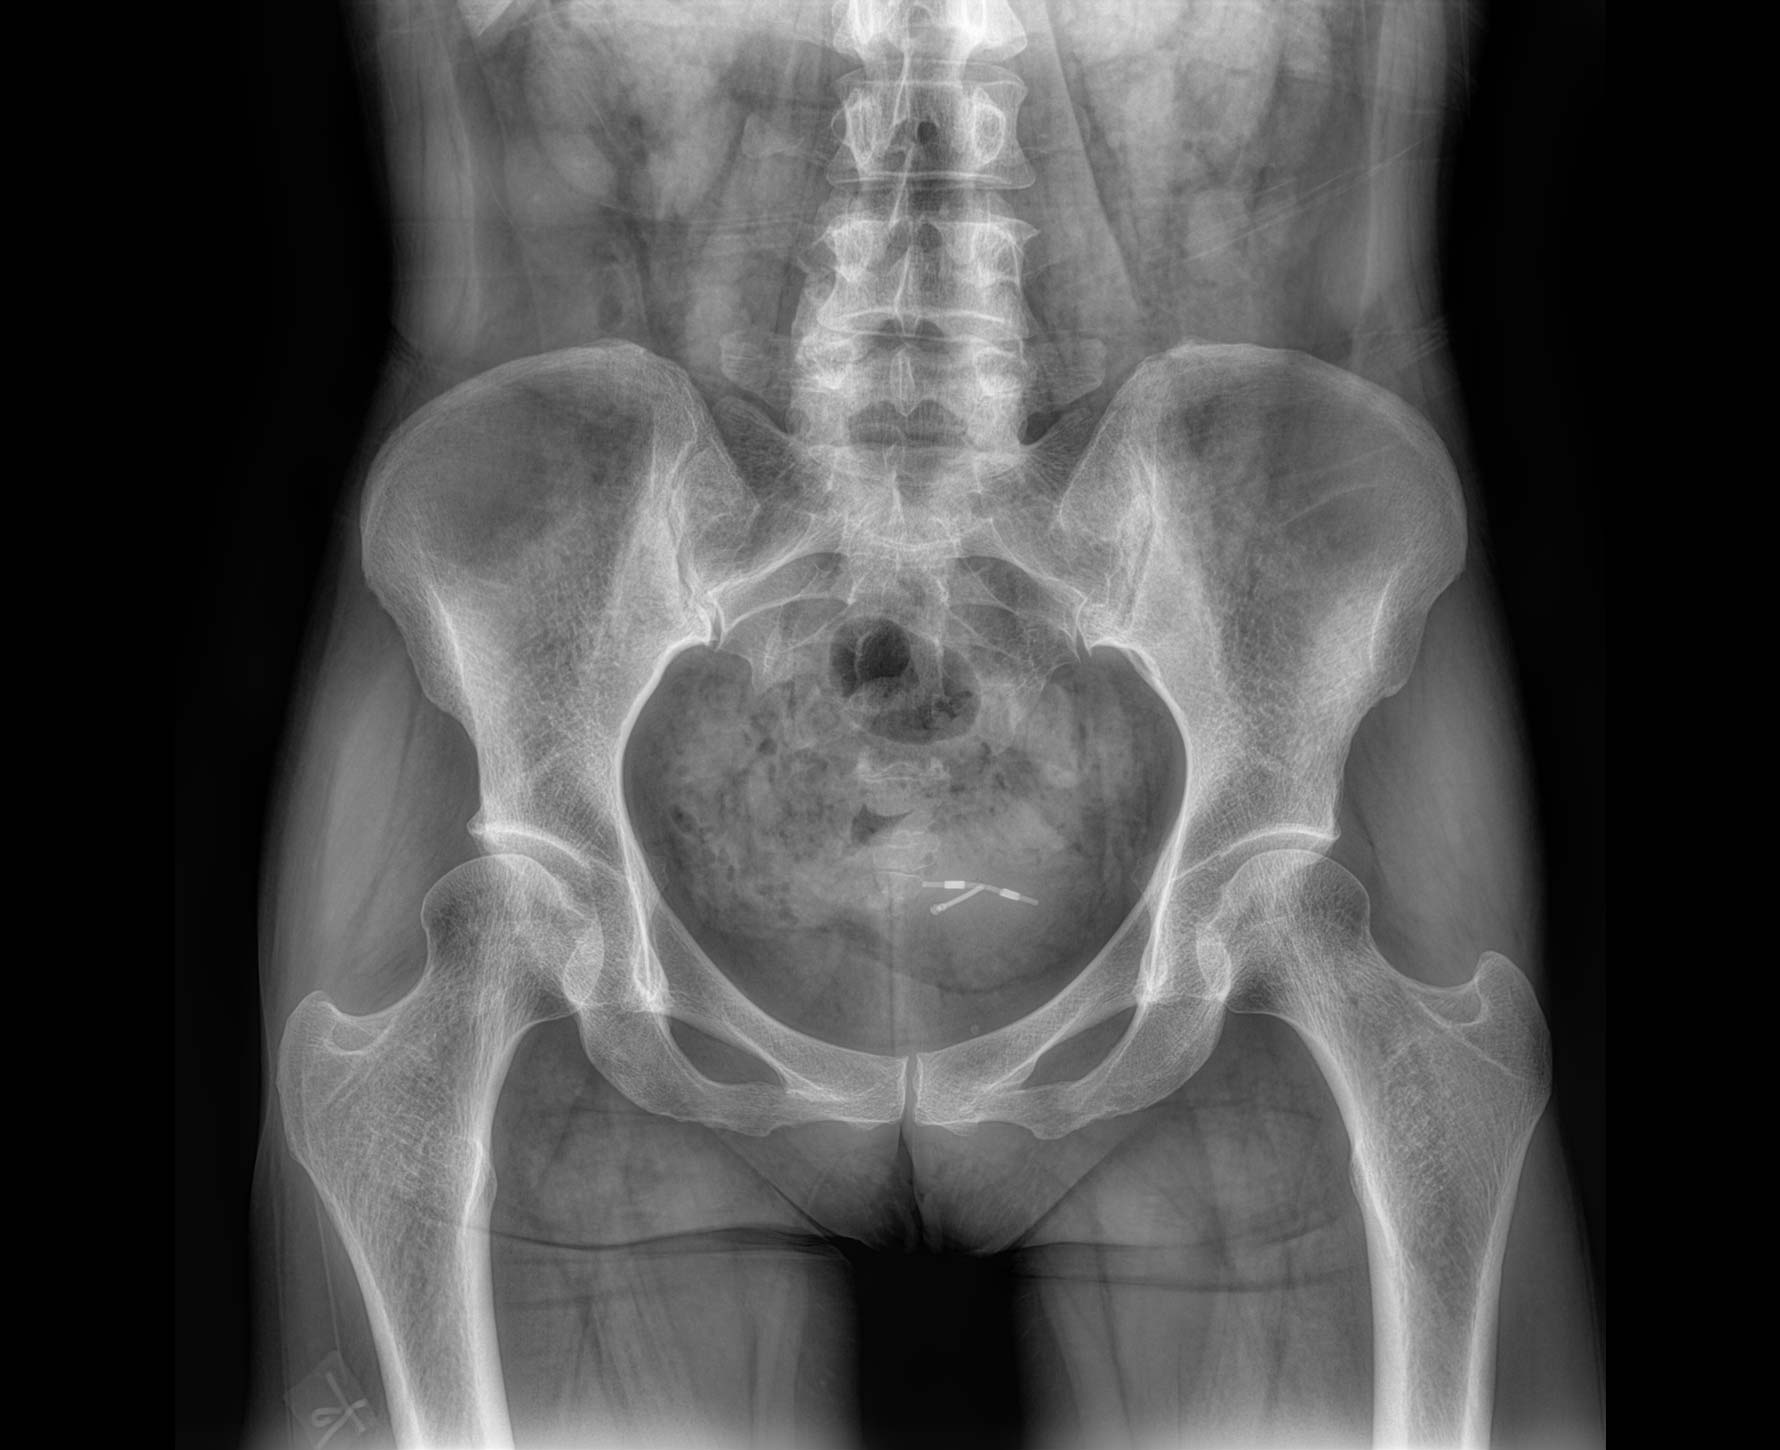

临床图像